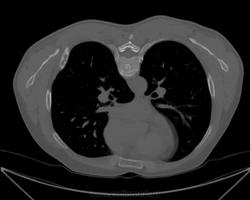

Во втором случае может быть остеохондрома, а в первом - мтс?

Во втором случае на мой взгляд, возможно "хондро", но вот какая "хондро" - это вопрос..., и не факт, что не хондросаркома.

В первом случая в дифряд поставил бы аневризматическую кисту и ГКО - на первые места.

Во втором случае написал хондросаркому, а первое заключение еще не отдал... Сомневаюсь что писать... Возраст около 50 обоим. В первом случае в анамнезе "какая-то дисплазия в тазобедренном суставе" со слов.

В первой случае выставил бы диф. ряд из ГКО, аневризматической кисты, хотя смущает отсутствие внутренней компактной пластинки, но при этом в полюса присутствует граница. Во втором случае выставил бы остеохондрому. А дальше, что гистолог подскажет.

Эх, гистологии бы по каждому представленному случаю представить.... а так, снова споры по диф.ряду...